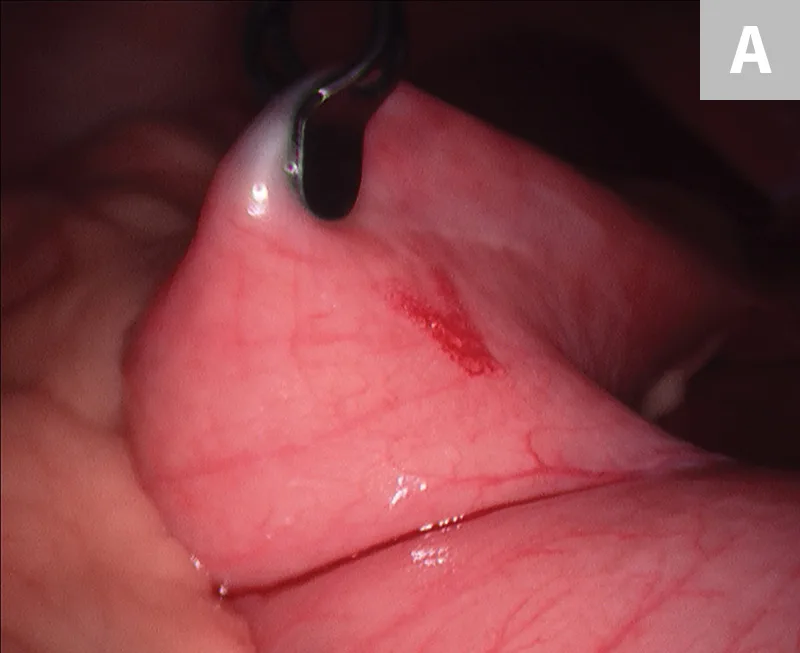

After placement of the 2 ports and insufflation of the abdomen, with the patient in dorsal recumbency, the pyloric antrum is grasped midway between the greater and lesser curvature (Figure 3A), and the antrum is elevated to the right lateral abdominal wall. The length of the paracostal port incision is enlarged. The pyloric antrum is exteriorized, and 2 stay sutures are placed at the oral and aboral extents of the proposed gastropexy site to stabilize the stomach and maintain exposure. An incision is then made in the pyloric antrum, similar in location to that made for a conventional incisional gastropexy. Each edge of the seromuscular incision of the stomach is sutured to the transverse abdominus muscle in a simple continuous suture pattern using a slowly absorbing suture material. The internal and external abdominal oblique muscles are reapposed over the gastropexy site using a simple continuous pattern, followed by routine closure of subcutaneous tissue and skin. Once the abdominal wall is closed, insufflation is re-established and the gastropexy site is examined for proper positioning before routine closure of the camera port site (Figure 3B).

FIGURE 3

10-mm Babcock forceps grasping the pyloric antrum during a laparoscopic-assisted gastropexy (A) and completed gastropexy with the pyloric antrum (black arrow) sutured to the right lateral abdominal wall (B; white arrow)